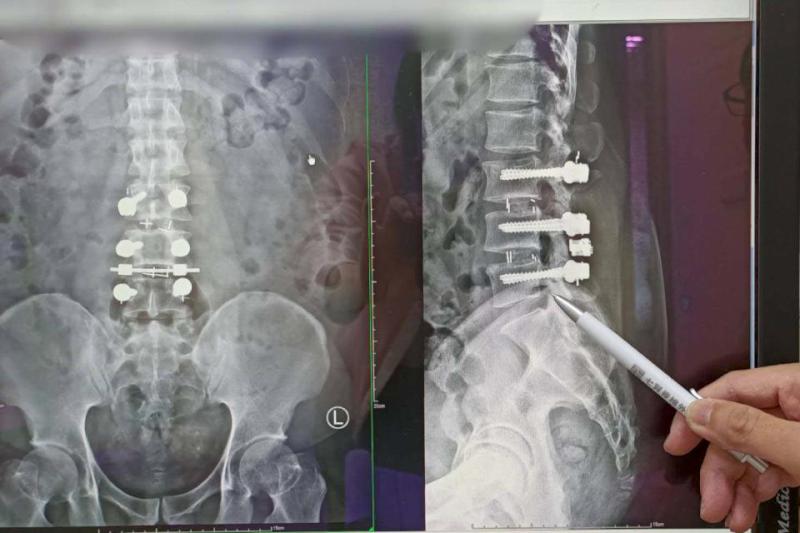

高市40歲朱姓男子民國99年在屏東從事工程業,35歲時常感腰痠背痛,甚至延伸腳踝,可謂坐立難安,手術未見改善,無法和友人打球及跑步,上網搜尋七賢脊椎外科醫院,經疼痛科副院長楊子旻確診腰薦椎椎間盤突出導致坐骨神經痛,建議施作高頻熱凝療法,術後隔天痛感消失,恢復正常生活,楊子旻說,高頻熱凝療法兼具疼痛感少、免住院、局部麻醉、未破壞神經阻斷痛覺等特性,透過電磁波加熱至42度,每秒刺激患部2次,每次20毫秒,適用坐骨神經、頸部、關節、五十肩、網球肘、背部、尾椎脊椎術後疼痛、足底筋膜炎等,治療後仍應維持理想體重、正確姿勢及避免搬重物,如有不適症狀速就醫檢查。圖/七賢脊椎外科醫院提供、文/高培德